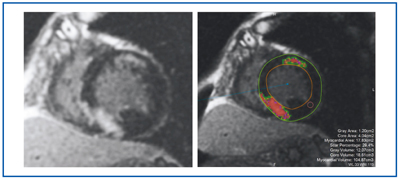

遅延造影は、われわれが対象とする心不全の心臓MRIでは、最も重要な検査法である。当院の撮像シーケンスはIR-GRE法である。遅延造影MRIは正常心筋をinversion recovery pulseによって抑制し、壊死または線維化して心筋に残った細胞外液性Gd造影剤の増強効果を見る検査である。本撮像も、従来は視覚のみでの評価が中心であった。ziostation2では、心内膜側および外膜側を輪郭抽出することで、遅延造影陽性領域をBull's eye表示できるほか、容積評価も可能となった。正常心筋に関心領域を設定し、その信号強度と標準偏差から決定した閾値をもとに、異常増強効果のCore領域とGray領域を抽出する。これらをカラーで表示するとともに、それぞれの面積(容積)を測定する(図6)。閾値は正常心筋信号の平均値と標準偏差の定数倍との和で定義され、定数はユーザーレベルで設定可能である。本手法を用いることで、視覚評価に加えて数値化した評価を加えることができ、より客観的に遅延造影を評価できる可能性がある。

図6 遅延造影 MRIのCore領域とGray領域のカラー表示と容積表示 図6 遅延造影 MRIのCore領域とGray領域のカラー表示と容積表示